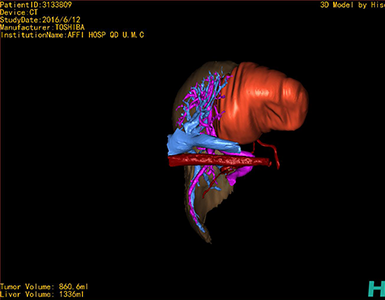

将0.625mm双源薄层CT资料的静脉期和动脉期Dicom格式文件导入海信CAS系统。

通过调节窗宽窗位调整CT序号,对肿瘤,肝实质,胆囊,下腔静脉,肿瘤,肝动脉、门静脉及肝静脉等进行三维重建;系统自动计算肿瘤体积和肝脏体积。

模拟手术操作,自动计算切除肿瘤体积。肝脏体积为1336ml,肿瘤体积为860.6ml,肿瘤体积为肝脏体积的64.4%,通过比对30-40岁正常肝脏体积为1323.35±298.47 ml,通过术前模拟手术,精准判断切除后剩余肝脏体积能耐受,避免肝衰竭发生。

术前三维重建:重建图片